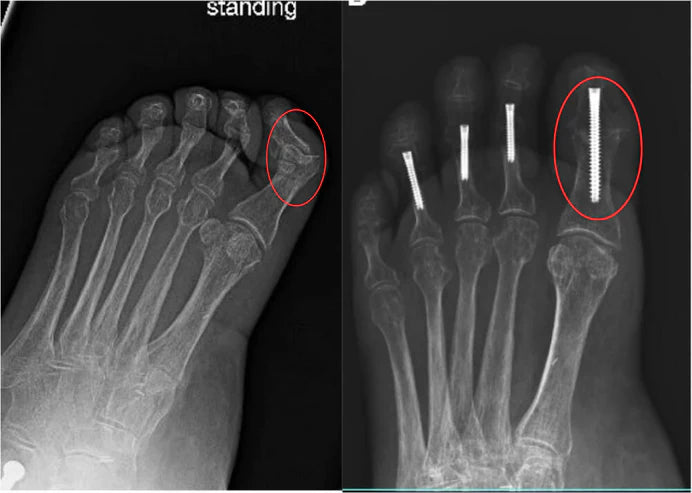

Why Hammer Toes Surgeries Fail

Up to 30–50% of hammer toes surgeries either fail or result in long-term stiffness, scarring, or pain returning.

Recovery? Expect 6–12 weeks off your feet, crutches, and the risk of recurrence if you don’t wear orthotics for life.

These surgeries often don’t address the root cause. They simply cut bone or fuse the joint, using pins or screws to force the toe straight.